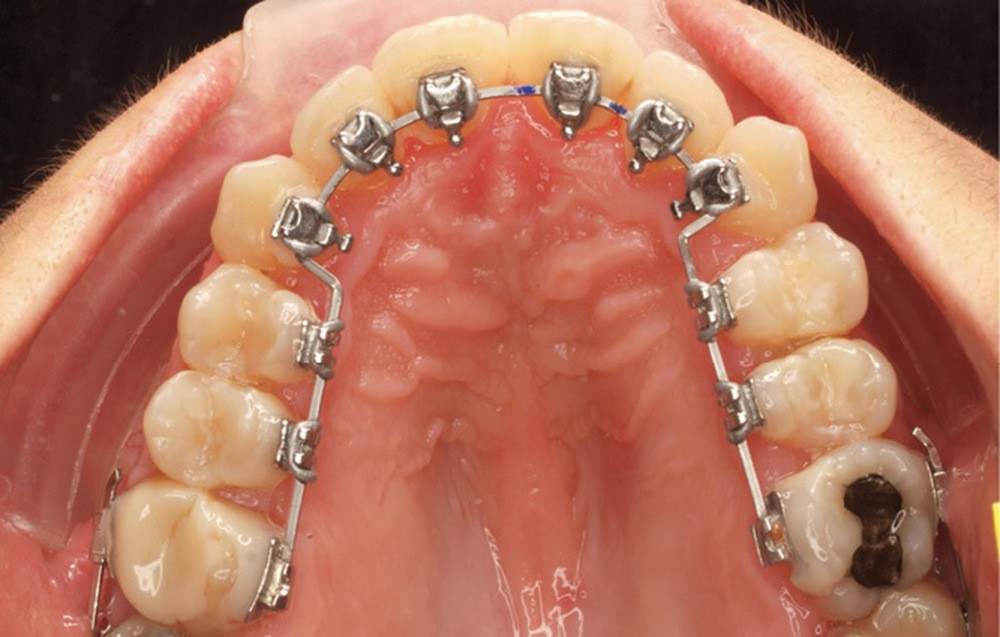

Correction

Le traitement est effectué avec un appareil lingual bimaxillaire et des attaches en .018 x .025 à insertion horizontale. L’appareil est réalisé intégralement au cabinet à partir d’un set-up conçu selon les objectifs décrits.

- Premier rendez-vous (fig. 2a) : l’arcade maxillaire est appareillée et un arc NiTi .014 en expansion est placé. L’arcade mandibulaire reçoit des cales rétro-incisives pour lever l’occlusion inversée. Par confort, des cales prémolaires, sans contact avec les dents antagonistes, sont posées pour réduire l’inocclusion latérale.

- Deuxième rendez-vous (fig. 2b) : les dents restantes sont collées et le même arc NiTi .014 est maintenu. Les cales rétro-incisives sont déposées et l’arcade mandibulaire est collée, un arc NiTi 0.014 posé.